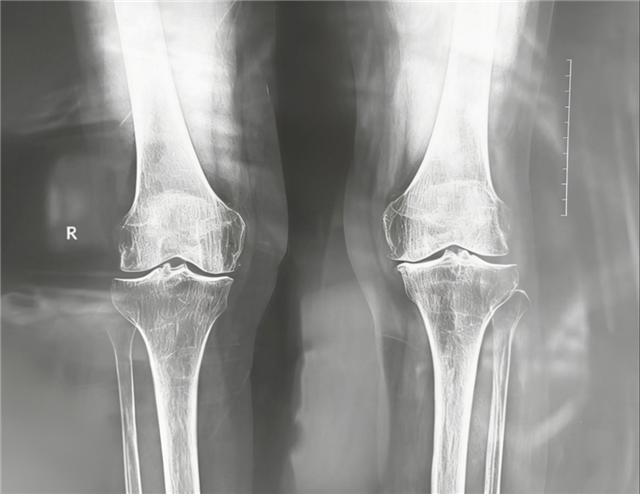

在长治市中医医院就诊后,骨伤科团队在张岩斌主任的带领下,为张奶奶做了详细的检查。影像结果显示:右膝关节间隙明显变窄,软骨磨损严重,是典型的骨关节炎。

术前影像资料